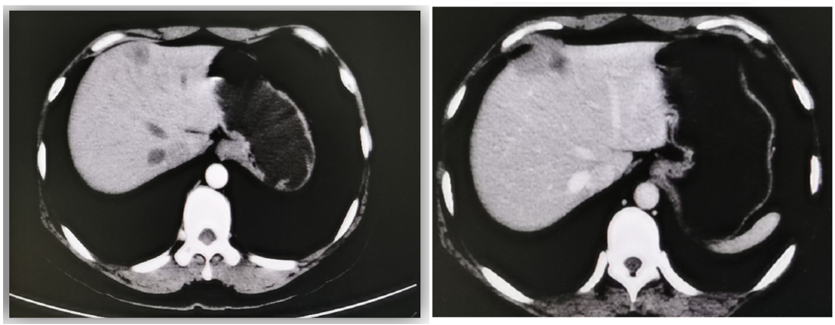

④复发转移:2017年12月(术后2年,内分泌治疗1年半)复查CT提示:左肺上叶尖后段胸膜下病变,转移瘤不除外。肝内多发低密度影,考虑转移。(图1)

图1.2017-12胸腹部CT:肝内多发低密度影,考虑转移。左肺下叶胸膜下病变,转移瘤待排。